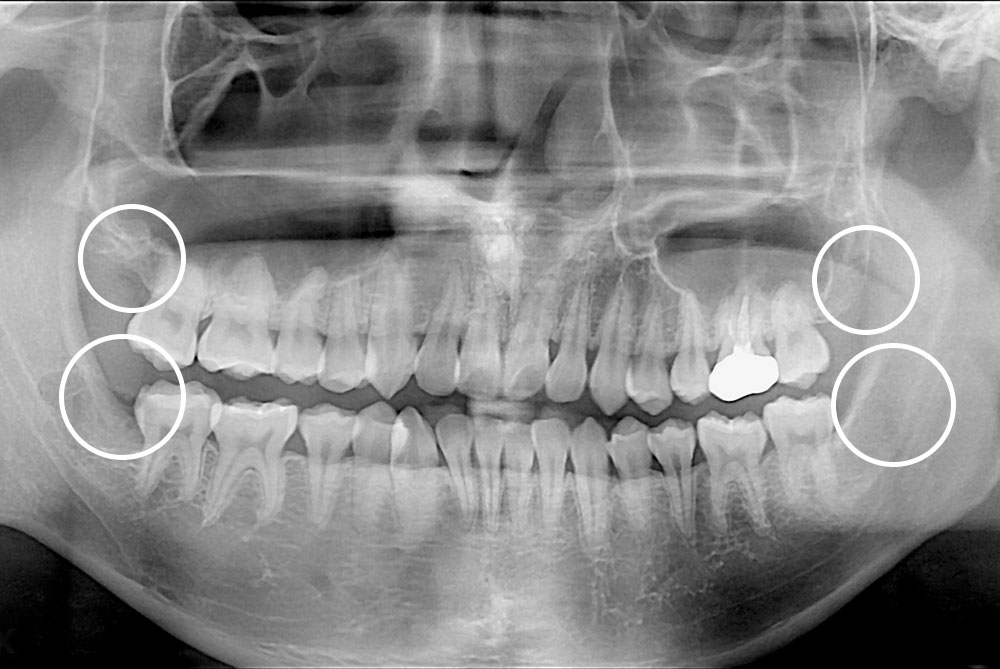

[사랑니] 매복 사랑니 발치

치료전 : 2019-01-24